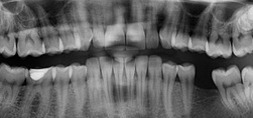

Types of Dental X-Rays

There are several types of dental X-rays, each serving a specific purpose in diagnosing and monitoring oral health.

- Bitewing X-rays are commonly used to detect decay between teeth and check the fit of dental restorations like crowns and fillings.

- Periapical X-rays provide a detailed view of the entire tooth, from the crown to the root, and are often used to diagnose issues in the root structure or surrounding bone.

- Panoramic X-rays capture the entire mouth in a single image, including the teeth, jaw, and surrounding structures, making them ideal for assessing impacted teeth, planning orthodontic treatment, or detecting bone abnormalities.

- Occlusal X-rays offer a view of the floor or roof of the mouth, helping to track the development of teeth in children or detect abnormalities like cysts or tumors. Each type of X-ray plays a key role in ensuring comprehensive dental care.